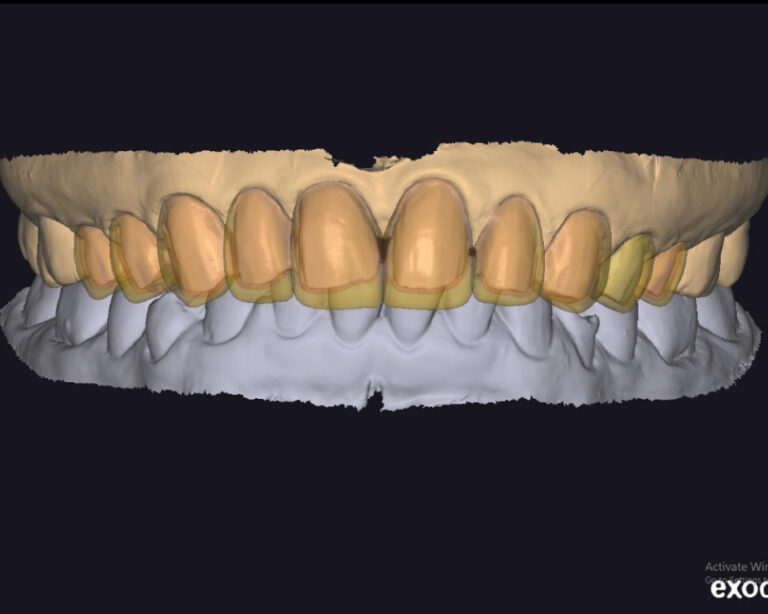

Case of the week